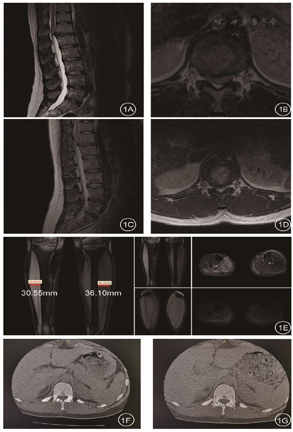

2020年8月12日彩超检查报告示(图1):甲状腺弥漫性病变;甲状腺双侧叶多发结节,考虑结节性甲状腺肿;甲状腺右侧叶较大结节,考虑滤泡肿瘤,建议细针穿刺活检(FNA);双侧甲状腺上动脉流速减低;双侧颈部未见明显肿大淋巴结。(甲状腺实质回声增粗,分布不均匀,内可见数个低回声结节,右侧叶结节大小约23mm×16mm不等,边界清,内回声欠均,较大结节周边见低回声晕;左侧叶见两个低回声结节,大小约4mm×3 mm不等,边界清,内部回声欠均匀)。